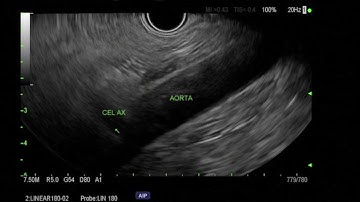

3/4/2025 procedure-celiac plexus block #lessinvasiveoption